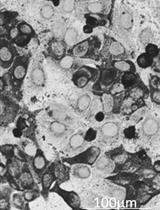

Confirm purification of neutrophil population by additional methods (e.g., cytospin).